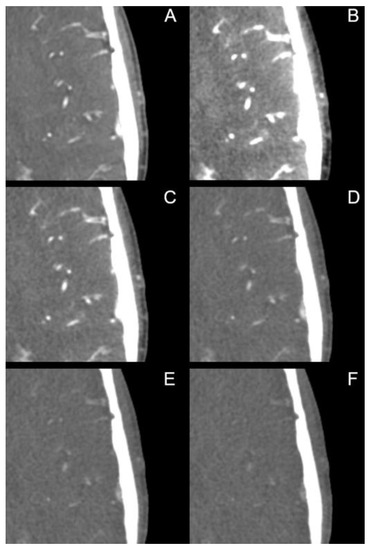

| Extracranial Arteries | PER | MER | p-Value |

|---|---|---|---|

| Signal | 377.15 ± 78.26 HU | 937.55 ± 204.71 HU (40 keV) | p < 0.001 |

| Noise | 12.23 ± 3.58 HU | 11.43 ± 3.38 HU (120 keV) | p < 0.001 |

| SNR | 33.03 ± 10.54 | 35.74 ± 15.65 (40 keV) | p = 0.003 |

| CNR | 58.72 ± 19.90 | 59.01 ± 22.68 (40 keV) | p = 0.447 |

| Intracranial Arteries | |||

| Signal | 342.76 ± 70.77 HU | 860.64 ± 200.45 HU (40 keV) | p < 0.001 |

| Noise | 14.18 ± 4.34 HU | 12.43 ± 3.60 HU (110 keV) | p < 0.001 |

| SNR | 26.73 ± 10.50 | 26.95 ± 13.22 (40 keV) | p = 0.901 |

| CNR | 52.25 ± 17.81 | 53.67 ± 21.68 (40 keV) | p = 0.775 |

| Cerebral Arteries | |||

| Signal | 323.68 ± 75.67 HU | 783.95 ± 206.30 HU (40 keV) | p < 0.001 |

| Noise | 13.88 ± 6.22 HU | 9.23 ± 4.61 HU (115 keV) | p < 0.001 |

| SNR | 28.60 ± 16.97 | 40.87 ± 66.94 (50 keV) | p < 0.001 |

| CNR | 48.53 ± 17.29 | 48.30 ± 21.75 (40 keV) | p = 0.181 |